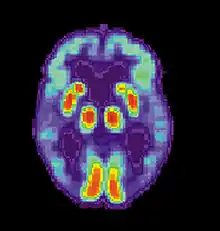

| Diagram of a normal brain compared to the brain of a person with Alzheimer's | |